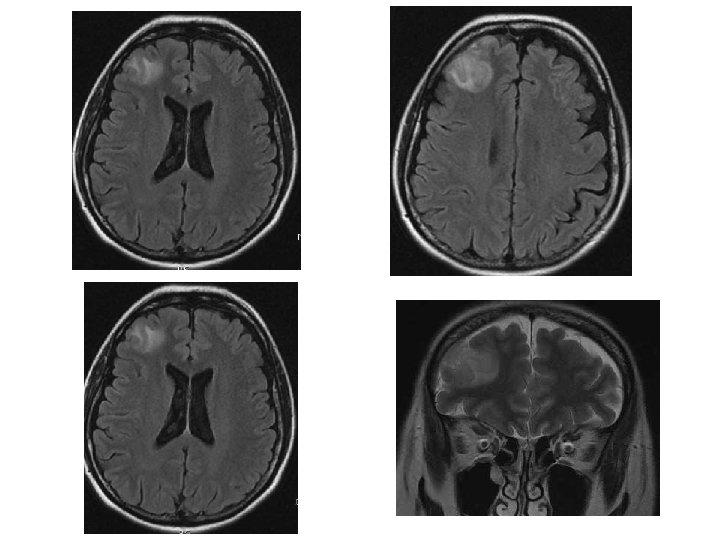

Femme de 43 ans ; crise généralisée inaugurale 51

52

53

54

Contrôle à 3 mois 55